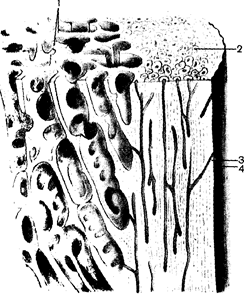

Каждая кость, оs, является самостоятельным органом и состоит из костной ткани. Снаружи кость покрыта надкостницей, periosteum, внутри нее в костномозговых полостях, cavitas medul-lares, находится костный мозг. Кости разнообразны по величине и форме, занимают определенное положение в теле. Для удобства изучения различают следующие группы костей: длинные (трубчатые), короткие (губчатые), плоские (широкие), ненормальные (смешанные), воздухоносные.

Длинная (трубчатая) кость, os longum, имеет удлиненную, цилиндрической или трехгранной формы среднюю часть – тело кости, диафиз, didphysis (от греч. dia - между, phyo - расту). Утолщенные концы ее называют эпифизами, epiphysis (от греч. epi-над). Каждый эпифиз имеет суставную поверхность, facies articuldris, покрытую суставным хрящом, которая служит для соединения с соседними костями. Участок кости, где диафиз переходит в эпифиз, выделяют как метафиз, metdphysis. Этот участок соответствует окостеневшему в постнатальном онтогенезе эпифизарному хрящу. Трубчатые кости составляют скелет конечностей, выполняют функции рычагов. Выделяют кости длинные (плечевая, бедренная, кости пред-плечья и голени) и короткие (пястные, плюсневые, фаланги пальцев).

СТРОЕНИЕ КОСТИ